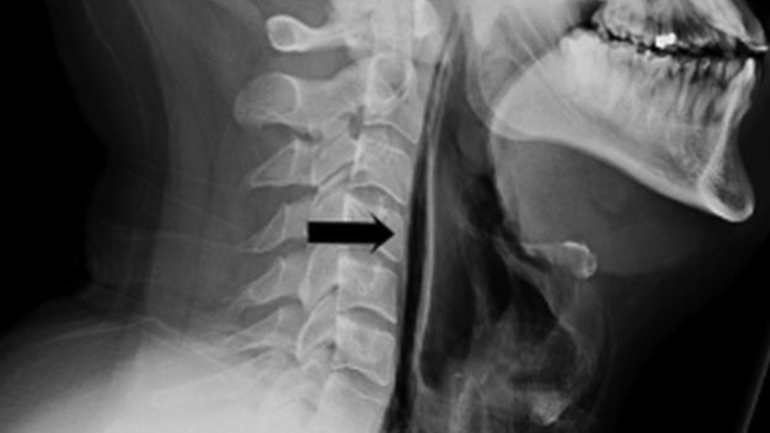

Röntgendeki siyah ok, boğazdaki (siyah bölge) yumuşak dokuya işaret ediyor.

Çekilen röntgen sonucu, nefes borusundan kaçan havanın boğazındaki yumuşak doku ve boyuna gittiği anlaşıldı.